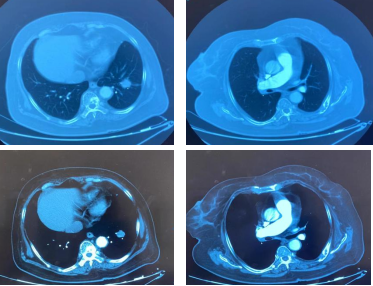

影像学-增强CT检查:左肺见不规则软组织影,包绕肺门结构,病变轴位长径约7.5cm,左肺散在结节影,最大约4.5cm;纵隔、肺门见多发淋巴结肿大,纵隔7组短径约2.0cm。

CT检查——基线

影像学-增强CT检查:治疗2周期后,左肺病灶明显缩小达52.9%,疗效评估为PR。

CT检查——治疗2周期后

治疗6周期后,左肺病灶明显缩小达58.6%,疗效评估为PR。

CT检查——治疗6周期后

治疗8周期后,左肺病灶较前增加,疗效评估为PD。

CT检查——治疗8周期后